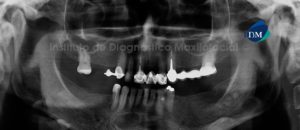

041 – Planificación y Tratamiento en Rehabilitación Oral con Prótesis sobre Implantes usando Análisis Cefalométrico

En los pacientes desdentados, que requieren una prótesis completa ya sea convencional o implanto soportada, los dientes artificiales se colocan en la prótesis completa por